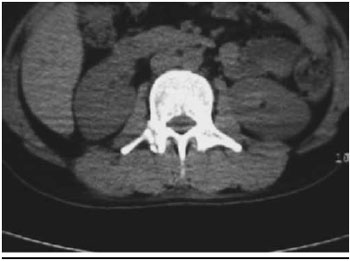

4 (Figura 2) e hematoma em músculo pssoas em regiao lombar, diagnosticados por tomografia computadorizada realizada no momento da internaçao. Houve relato de perda de consciência no local do trauma por tempo indeterminado. Paciente foi internado hemodinamicamente estável.

Figura 2 - Fratura de processo transverso de vértebra lombar.